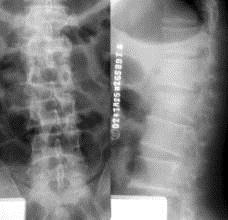

病历摘要: 患者×××,男性,21岁,不慎从3米高处坠落,双足着地,出现双足跟肿胀疼痛,腰痛不能站立。查体:腰1棘突有压痛和叩击痛,双足足跟部肿胀,触痛(...

问题 病历摘要: 患者×××,男性,21岁,不慎从3米高处坠落,双足着地,出现双足跟肿胀疼痛,腰痛不能站立。查体:腰1棘突有压痛和叩击痛,双足足跟部肿胀,触痛(+),双下肢感觉正常,双足伸足母、伸趾正常,双膝关节伸屈正常。 该患者的治疗以下叙述哪些是正确的?

选项 A、后入路椎板切除减压+椎弓根钉内固定 B、后入路椎板切除减压 C、后入路椎弓根钉内固定撑开复位,植骨融合 D、侧方前入路腰1椎体切除椎间植骨融合+椎体钉内固定 E、保守治疗卧床3个月

答案 CE